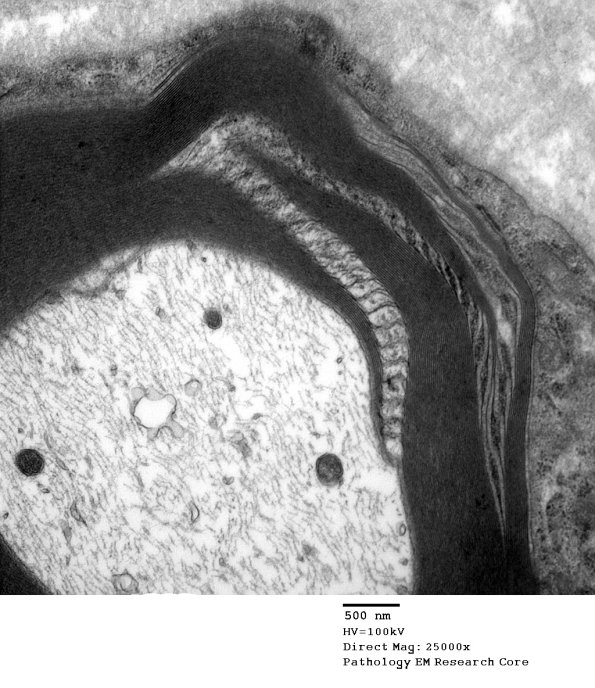

Again, a single microtubule is prominent in the leaflets of this SLC. (Electron micrograph)